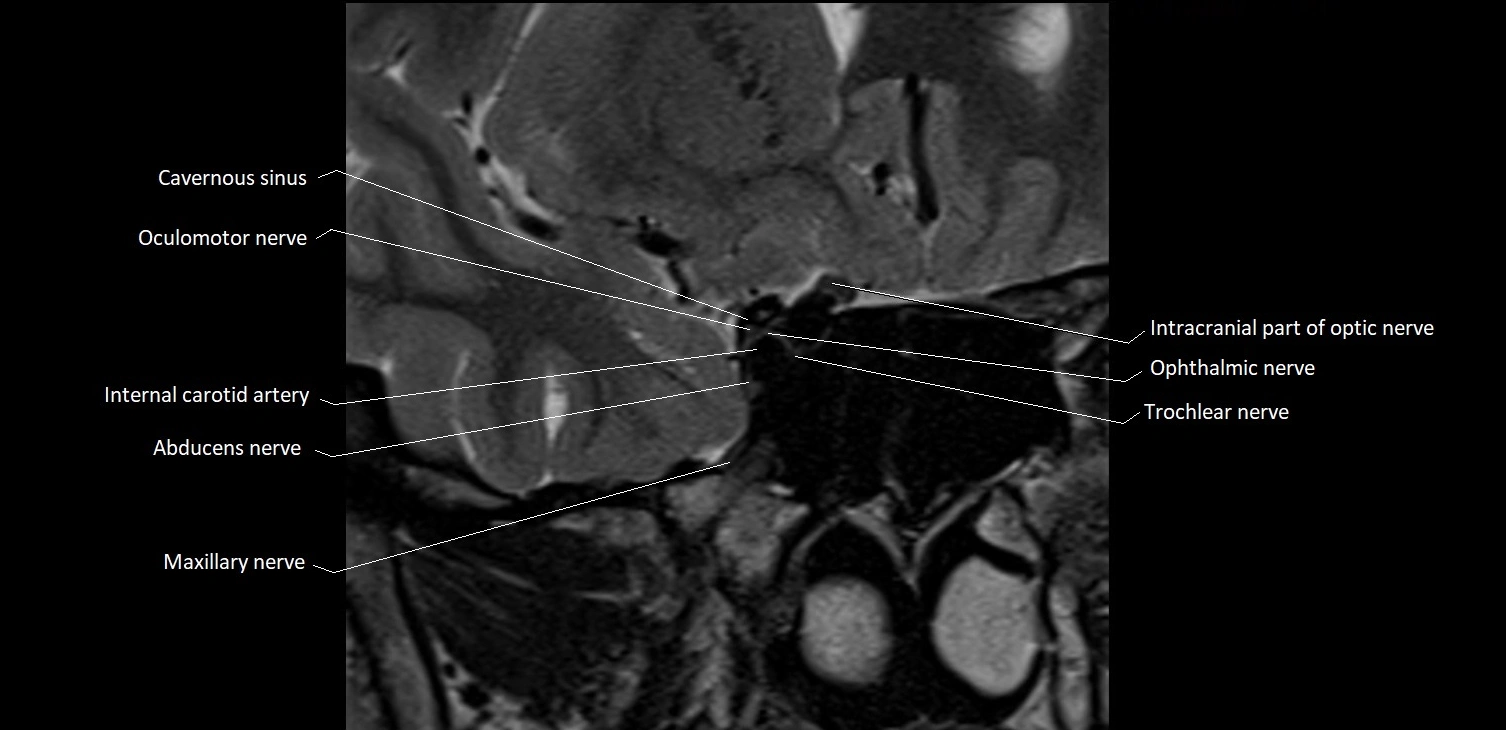

MRI Appearance

-

The abducens nerve is a small, thin, linear structure

Best visualized on high-resolution T2-weighted 3D MRI sequences (e.g., FIESTA or CISS)

Seen as a hypointense (dark) line running from the brainstem at the pontomedullary junction, traversing the prepontine cistern, and entering Dorello’s canal under the petrosphenoidal ligament, then into the cavernous sinus, and finally the orbit

May be challenging to visualize in standard MRI due to its small size

Pathology may be inferred by absence, displacement, or enhancement of the nerve

MRI images